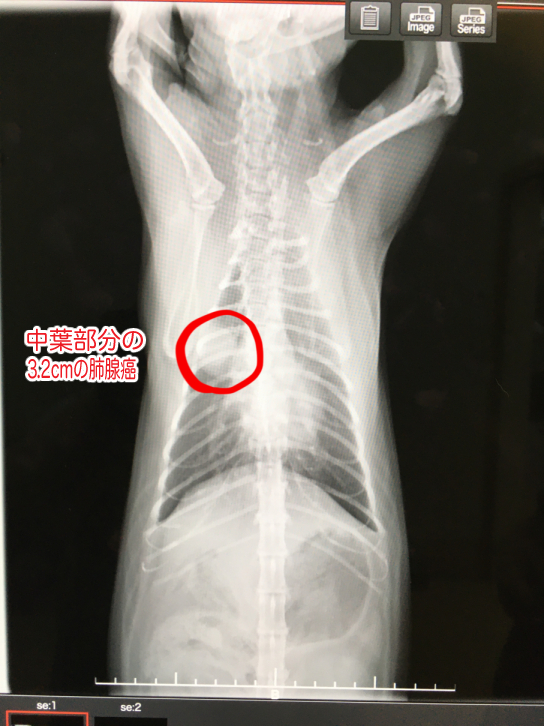

早急に診察して頂き、獣医師の説明によれば『ご家族の皆さん、入って来て下さい』との一声から始まり、『雨助君は大動脈血栓塞栓症ので、普通は心筋症から起こる症状だけど、今の雨助の心臓を見ても考えにくく、何処からきたのかわからない。大動脈血栓塞栓症との診断を受けると、自分が知ってる今までのワンちゃんネコちゃんは24時間以内に99%の確率で亡くなっている…あと、右肺に肺腺瘤が見つかりました。猫の肺腺癌の症例は少ないが、肺腺癌で間違いないと思う。』とのこと、『大動脈血栓塞栓症は24時間が峠、越えれば次は脚が少しでも動ける様に、72時間が勝負になる』ということでした。

レントゲンで見つかった肺腺瘤(肺腺癌の疑い)や大動脈血栓塞栓症の状態確認へCTの撮れる、日本で技術のある腫瘍の専門医の先生を紹介していただき、先日訪問し検査をしました。

10月1日 肺腺瘤(肺腺癌の疑い)と確認。ほぼ肺腺癌で間違いないので転移してないから早急に取ったほうがいい。と言われました。

此方の獣医師によれば大動脈の血栓は2箇所、現在血が通っているのが不思議とのこと、また腫瘍がかなり大きかったにも関わらず、転移がみられなかったことが命を少しでも延ばせるかもしれないということでした。

画像は、3.2cmの肺腺瘤(肺腺癌疑い)です。猫の肺腺瘤(肺腺癌疑い)は症例が少なく、開胸手術等や高度になるため、費用がとても高額になります。